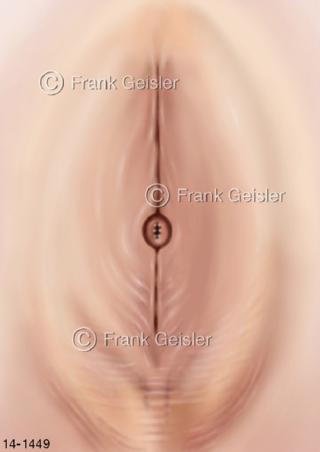

Bildergalerie Urogenitalsystem

Bilder zum Urogenitalsystem mit Urogenitalorgane, Urogenitaltrakt, zum Harn- und Geschlechtsapparat, Harnorgane und Geschlechtsorgane, Organe der Harnwege und der Fortpflanzung, Harnorgane und Geschlechtsorgane im männlichen und weiblichen Urogenitalsystem